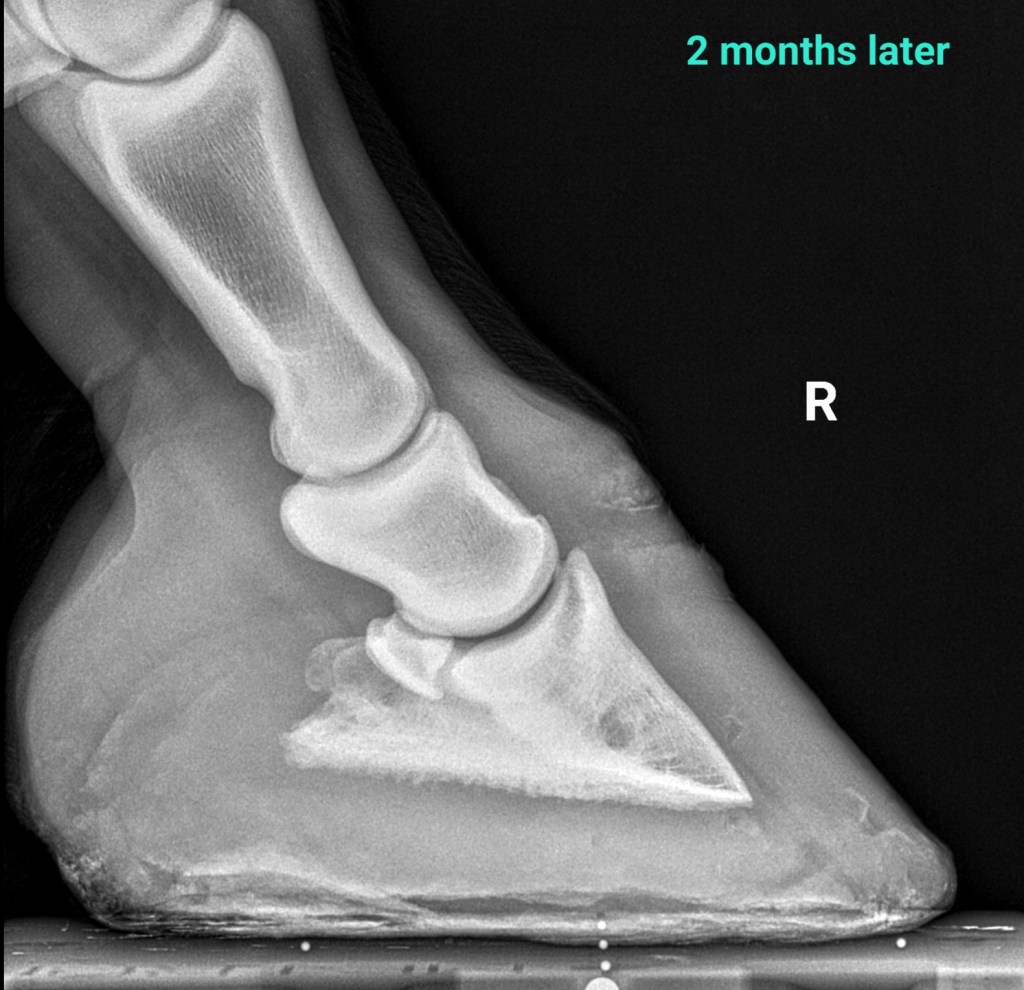

2 months later the horse is sound, he has doubled his sole depth, and improved alignment. I gradually reduced the size of heel elevation and finally removed the Ultimates.